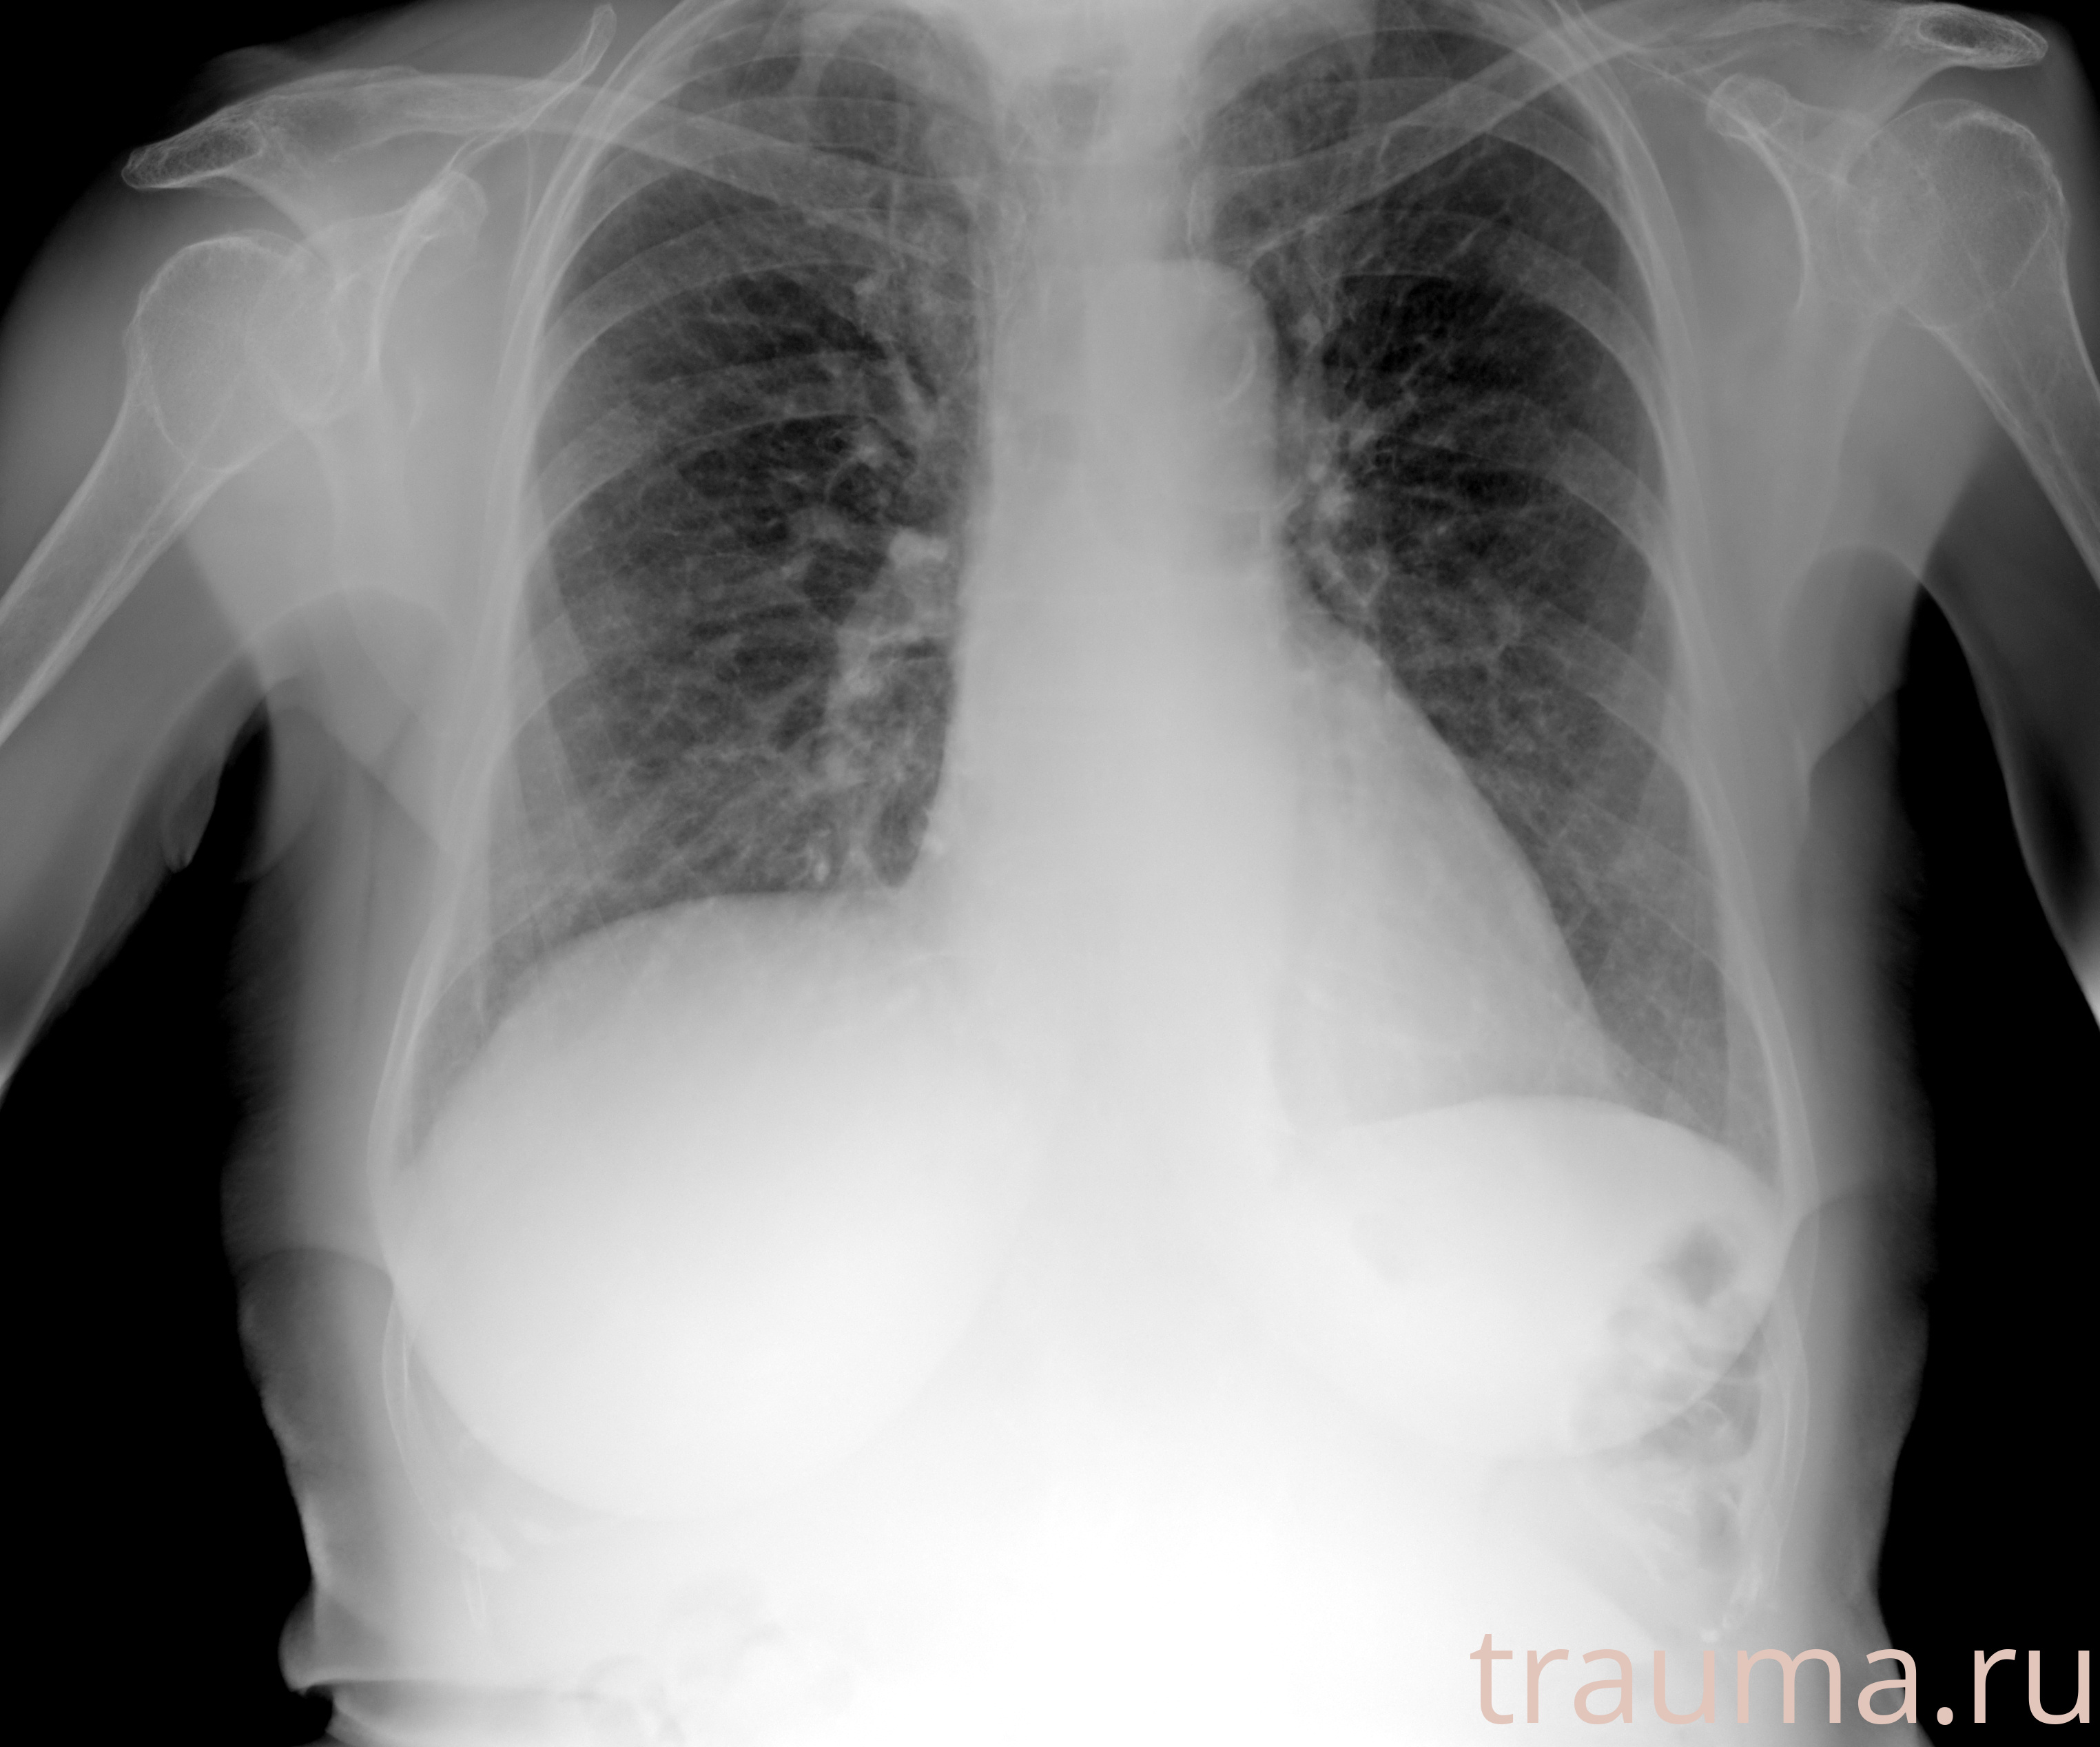

Рентгенограммы

Рентген на дому: по вашему адресу приезжает врач-рентгенолог, травматолог-ортопед с мобильным рентгеновским аппаратом, проводит диагностику травмы или заболевания, делает необходимые рентгенограммы, дает рекомендации по дальнейшему лечению. Получить качественные снимки в домашних условиях возможно благодаря уникальной методике, разработанной МосРентген Центром для института  Склифосовского